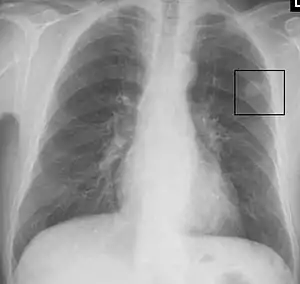

![]() | |

| A coronal CT scan showing a malignant mesothelioma Legend: → tumor ←, ✱ central pleural effusion, 1 & 3 lungs, 2 spine, 4 ribs, 5 aorta, 6 spleen, 7 & 8 kidneys, 9 liver | |